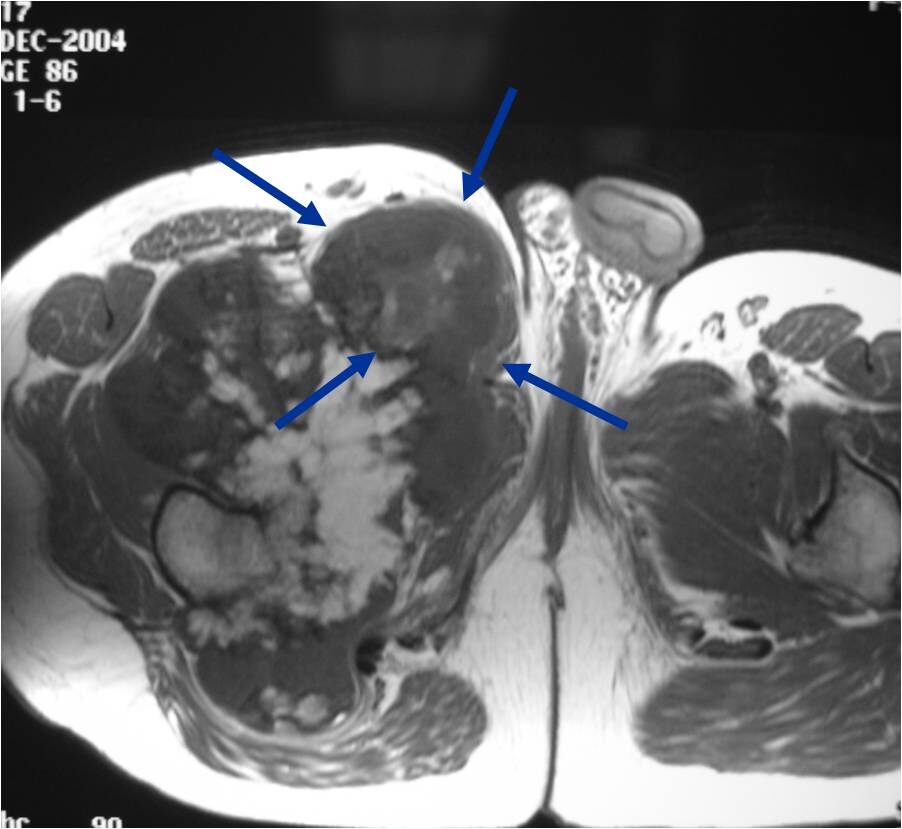

- Best test for evaluating thickness of cap and surrounding bursa

- Intermediate T1W Images

- High Intensity T2W Images because of fluid content

MRI: Secondary Chondrosarcoma of Proximal Femur: Thick Cartilage Cap (>2cm)